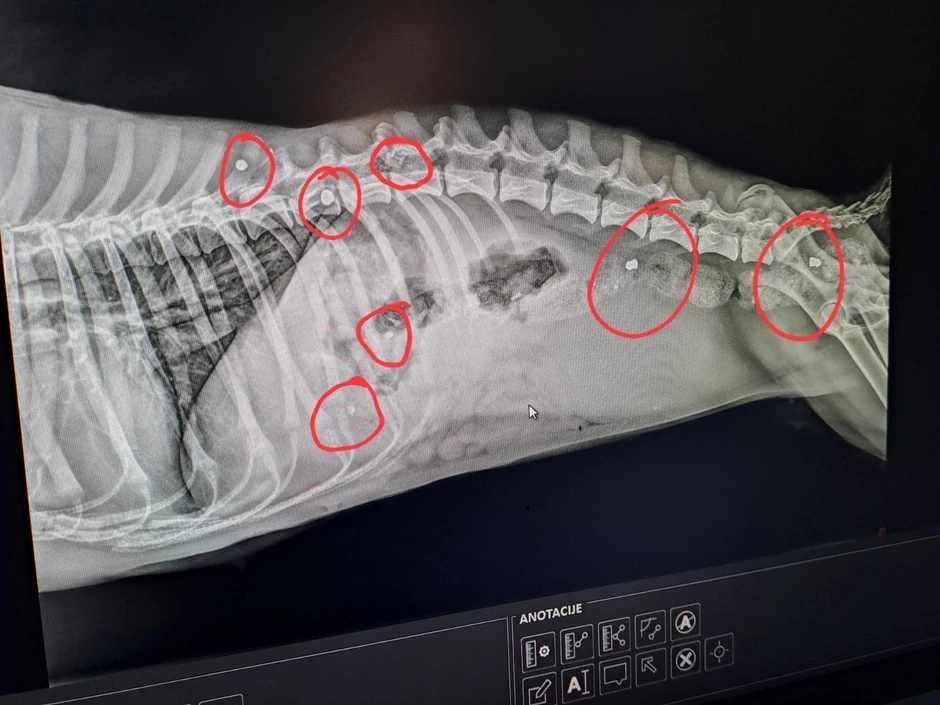

Rendgen je otkrio jezivo saznanje.

- Na snimku smo videli sedam metaka u njenom telu, od kojih je jedan bio zaglavljen u kičmi. Prvo smo se čudili kako je preživela, a onda sam se pitao koji monstrum je mogao takvu stvar da uradi štenetu - navodi naš sagovornik.

I beogradski veterinar bio je zatečen. Ženka mešanca verovatno će zauvek ostati nepokretna, ali je toliko bila jaka da preživi krvničko nasilje osobe koja je u nju ispalila sedam hitaca.

- Prognoze nisu sjajne, ona će verovatno do kraja života biti pas koji neće moći da hoda. Sada joj sledi operacija, svi meci će biti izvađeni, a onda ide oporavak koji će biti veoma težak i kasnije adaptacija na život koji će živeti kao nepokretan pas - kaže za "Blic" Ivan i pita se: